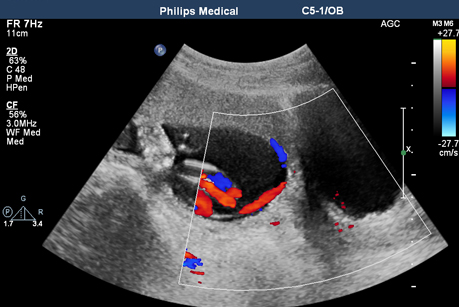

日前,一名28岁的孕妇(孕 2产0)孕23周来我院超声科做产前筛查。蔡国静副主任医师凭借自己丰富的临床经验及严谨细致的工作作风诊断孕妇为“帆状胎盘合并血管前置”。

我院产科在35周时将孕妇收住院,入院后严密监护,于35+3周时实施剖宫产,成功娩出一体重2110g的女婴,帆状胎盘合并血管前置在术中得以证实。

帆状胎盘是指脐带附着于胎膜上,脐血管在未进入胎盘时已发生分支,经过羊膜和绒毛膜之间进入胎盘。当胎膜中的脐血管接近或跨越宫颈口,位于胎先露之前,则称为血管前置。血管缺乏华通胶及胎盘组织的保护,容易受压及撕裂,引起胎儿出血,导致胎儿死亡。产前前置血管破裂大量出血,胎儿可在3分钟内死亡,死亡率高达58%-73%;或者胎先露下降血管受压,胎儿循环障碍,导致胎儿窘迫甚至死亡。

据了解,血管前置如果能在产前得到诊断,胎儿存活率达97%,而没能得到诊断的存活率仅为44%,这是我院首例成功产前正确诊断并及时处理的病例。此孕妇的转危为安,需要超声医师耐心、细致地寻找蛛丝马迹,也需要产科及时、正确的处理。在现代医疗诊疗模式的发展趋势下,多学科通力协作显得尤为重要。在以后的工作中,我们还是要继续提高专业技术水平,多学科紧密合作,精益求精,脚踏实地不断向前迈进。